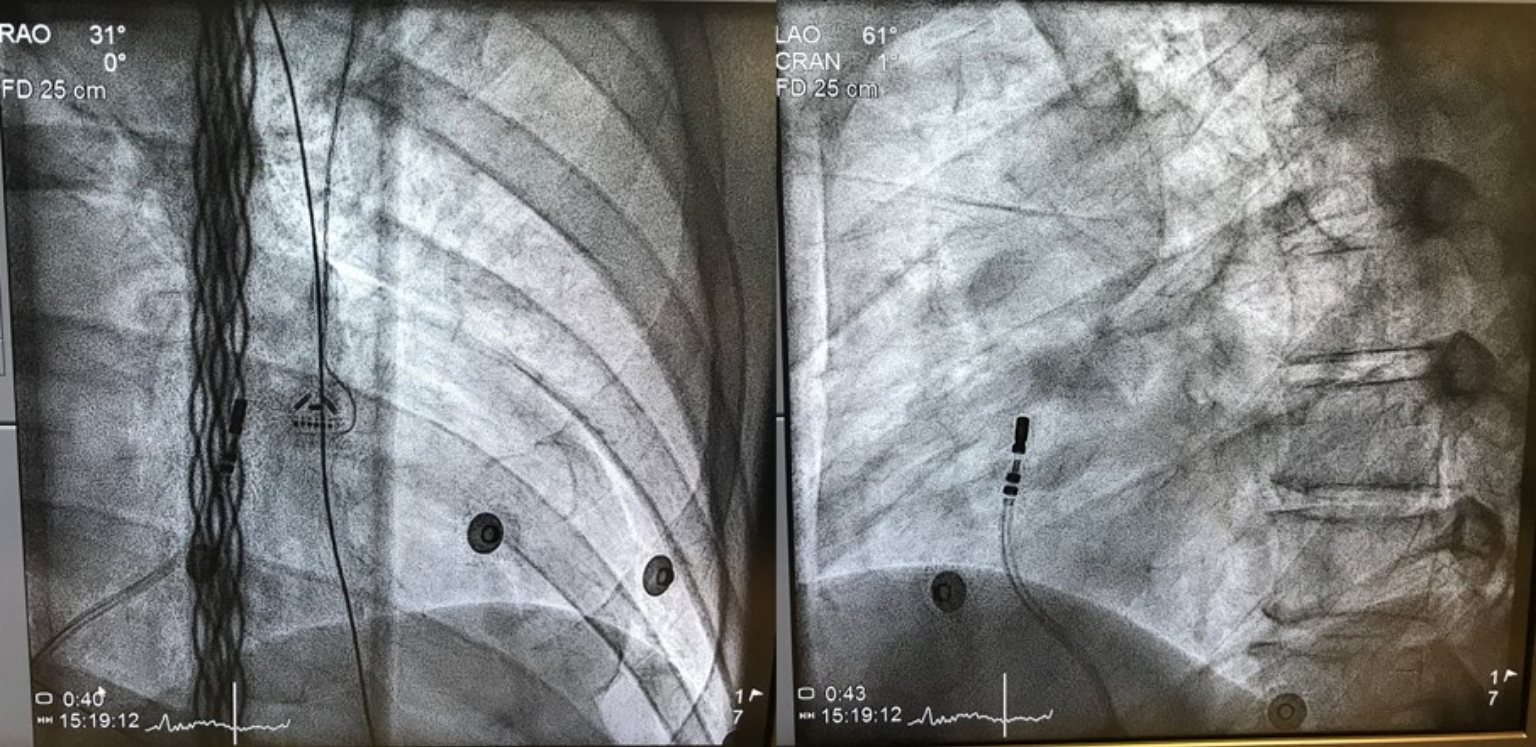

最後,這位女士接受3D立體定位系統燒灼術,精準地消滅了在右心室出口的病灶,心臟終於不再亂跳,也不用吃藥,快樂逍遙去了。